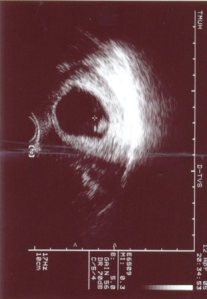

產檢

從每個月一次,變每兩週一次,最後每週一次

每一對準備迎接新生命的準父母們一定都有過的經驗

從第一次在超音波螢幕上看到兩顆球狀形體,每隔一次就更有形些

後來甚至看得出是不是正在動,每一次都教人無比興奮,沒錯吧^^

小P的唐氏症指數報告出來時,機率是數百分之ㄧ(代表機率很高)

當場聽從醫師建議做羊膜穿刺術,以更進一步篩檢

然後還得靜待隔週報告出爐,做完的那一刻,老王不禁潸然淚下

現再回想起那一刻,突然覺得只要小p健康活潑,其他都不是那麼重要了(皮照打XP)